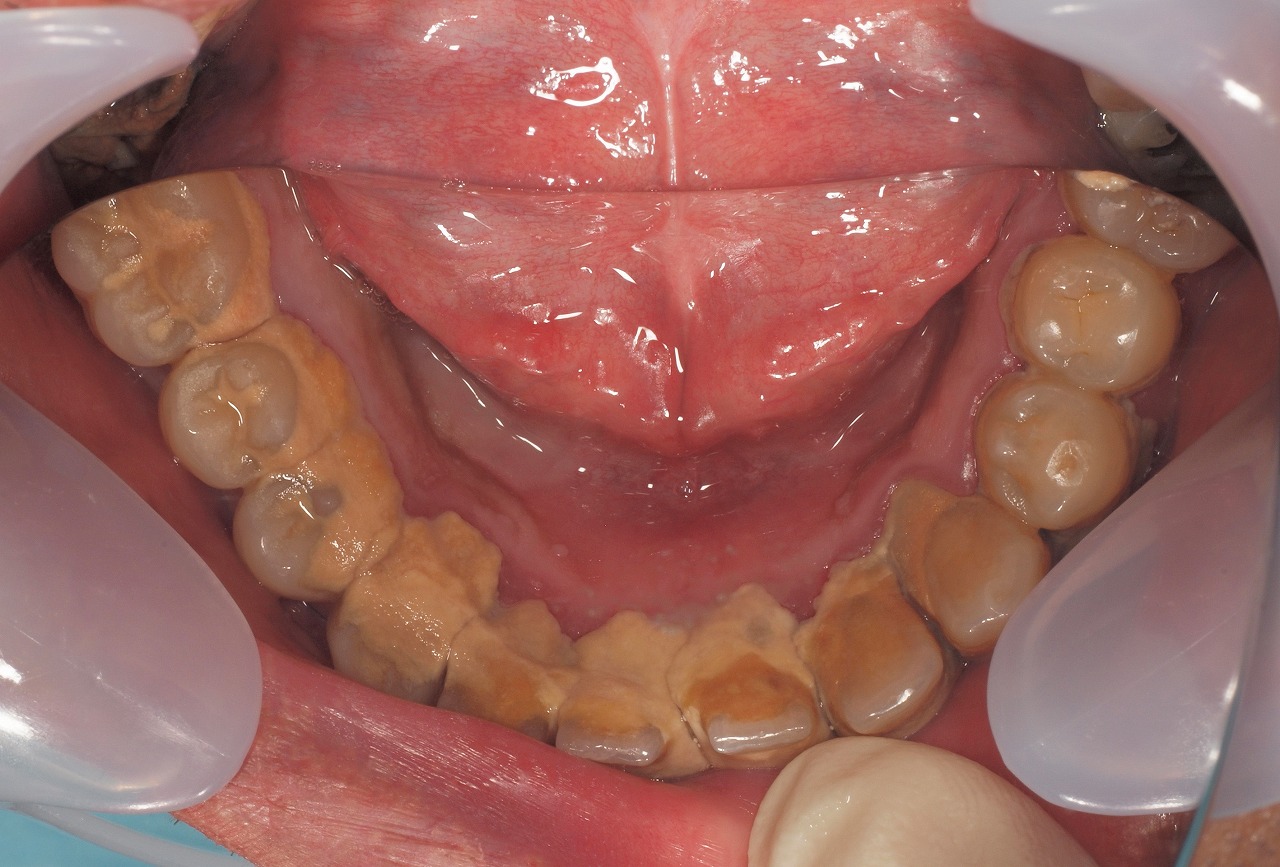

ブログ一覧|広島市安佐南区の歯科医院 ブログ一覧 トップ ブログ一覧 お知らせ スタッフブログ ブログ一覧 スタッフブログ 2018/01/19 内視鏡の実践トレーニングの様子になります。 若手の先生まであらゆる先生ができるようにもっていくように日々トレーニングを積んでいます。 2018/01/18 アマルガムやり変え。適合が悪くなったものも治療対象になります。 2018/01/18 虫歯からのセラミック治療へ。 2018/01/18 詰めてある樹脂の下で虫歯が蔓延し、神経が感染して死んでいる場合もあります。 2018/01/18 セラミック治療へ。 こんな感じで虫歯の治療より審美治療へ変わります。 2018/01/18 セラミックによる虫歯から審美治療。 2018/01/17 虫歯が大きくて根の治療からのセラミック治療。 2018/01/17 SET時の口腔内写真になります。 グラグラで抜歯も余儀なくされた歯もありますが、、もう一度咬合再構成を図りました。 << 1 2 3 4 5 … 772 773 774 775 776 … 870 871 872 873 874 >> Web診療予約 初めての方へ 選ばれ続ける理由 院内設備について 歯が痛いしみる一般歯科 歯がぐらぐらする歯周病 健康な歯を保ちたい予防歯科 子供の虫歯予防をしたい小児歯科 銀歯をセラミックに審美歯科 白い歯を目指しませんか?ホワイトニング 矯正専門医がいるので安心矯正歯科 抜けた歯を補いたいインプラント・入れ歯 医院案内 スタッフ紹介 メリィハウス歯科クリニックオフィシャルホームページ ラベンダー歯科クリニックオフィシャルホームページ お知らせ・ブログ ホーム 診療科目 一般歯科 歯周病治療 予防治療 小児歯科 審美治療 ホワイトニング 矯正歯科 入れ歯・インプラント マウスピース矯正 初めての方へ 院長・スタッフ 設備紹介 医院案内・アクセス メニューを閉じる